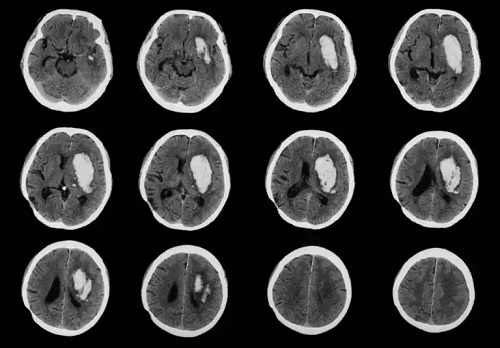

O observație importantă este faptul că tumorile cerebrale nu apar niciodată ca noduli în exteriorul capului. Pe măsură ce tumorile cerebrale modifică celulele creierului, cancerul se dezvoltă în interiorul acestui organ.

Această boală nu dăunează niciodată neuronilor, deoarece aceste celule ale sistemului nervos nu sunt afectate de diviziunea celulară. Prin urmare, această patologie va afecta celulele gliale, adică celulele care însoțesc, hrănesc și protejează neuronii.